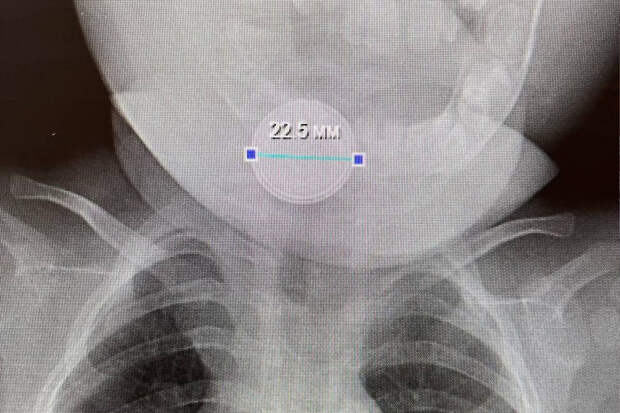

В приемное отделение больницы села Казанское был доставлен десятиместный младенец, ребенок с трудом дышал, сильно кашлял и вел себя беспокойно. В ходе обследования медики обнаружили в желудке маленького пациента инородное тело — круглую батарейку.

Было принято решение о проведении хирургического вмешательства, опасный предмет удалось извлечь. Батарейка не успела нанести существенного вреда здоровью ребенка.